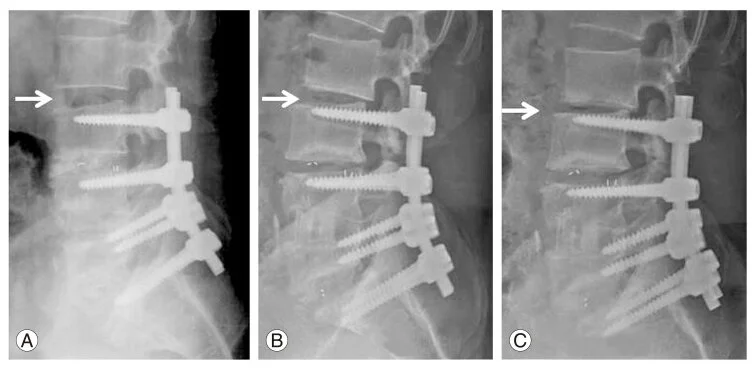

This series shows one of the major complications of spinal fusion, adjacent level breakdown, which occurs in roughly 30 – 50% of patients in the 5 – 10 years after fusion. In this series you can see the disc above the fused levels collapse in the 18 months after a 3-level fusion due to increased stress and motion related to the fusion below.

As a result, this fusion is extended to the next level in panel F. Adjacent level degeneration represents a major worry for patients and physicians.